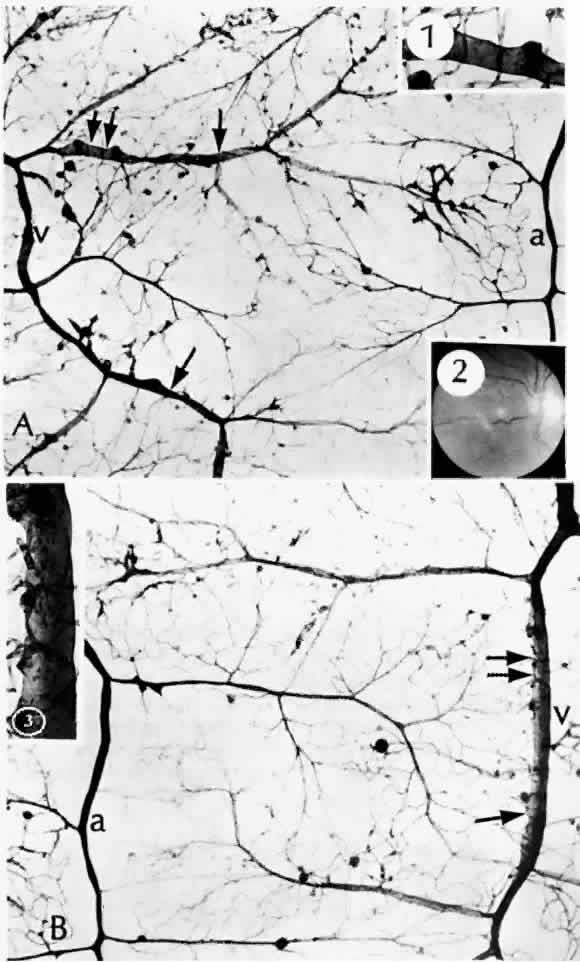

The retinal veins can also become irregular and tortuous with sausage-shaped dilatations. The vascular walls become diffusely permeable so that they both leak and stain with fluorescein. These changes also seem to be associated with ischemia. As shown by trypsin digestion, the beaded areas are hypercellular (Fig. 10).43 Diabetes is also a risk factor for branch retinal vein occlusion47 and central vein occlusion.43

Fig. 10. A and B. Sausage-shaped venules (arrows) result from irregularities in the venular walls. Note the arteriolar-venular connections and thickened capillary basement membranes (dark-colored capillaries). Retinal capillary microaneurysms tend to arise from cellular (viable) capillaries and cluster around acellular (nonviable) capillaries. The venular walls not only are irregular, but they also have an unusual presence of saccular microaneurysms (Inset 1, and Inset 3 from the area of the double arrows). Inset 2. Fundus appearance of microaneurysms, a cotton-wool spot, irregular venules, and intraretinal neovascularization in the form of a rete mirabile. (a = arteriole; v = venule) (A and B, PAS, × 16; Inset 1, PAS, × 40; Inset 2, fundus; Inset 3, PAS × 54)

Other capillary changes, more severe and extensive than microaneurysms, are collectively termed intraretinal microvascular abnormalities (IRMAs). Clinically, these manifest as dilated channels that leak fluorescein and show vascular wall staining (Fig. 11). De Venecia and co-workers36 were able to distinguish between IRMAs arising from arteriolar capillaries and IRMAs arising from venular capillaries. The IRMAs associated with arterioles exhibited early filling and late leakage on angiography. Histologically, they appeared as solid proliferations of endothelial cells, adjacent to acellular capillaries. In some instances, they may represent true intraretinal neovascularization. The IRMAs adjacent to venules filled in the early venous phase and leaked late. Histologically, they were irregularly dilated, had thin walls, and may have represented shunts.

Fig. 11. Arteriolar-venular connection (collateral) consists of a dilated cellular capillary (arrow) with an increased number of anuclear (apparently nonviable) capillaries. (PAS, × 16)